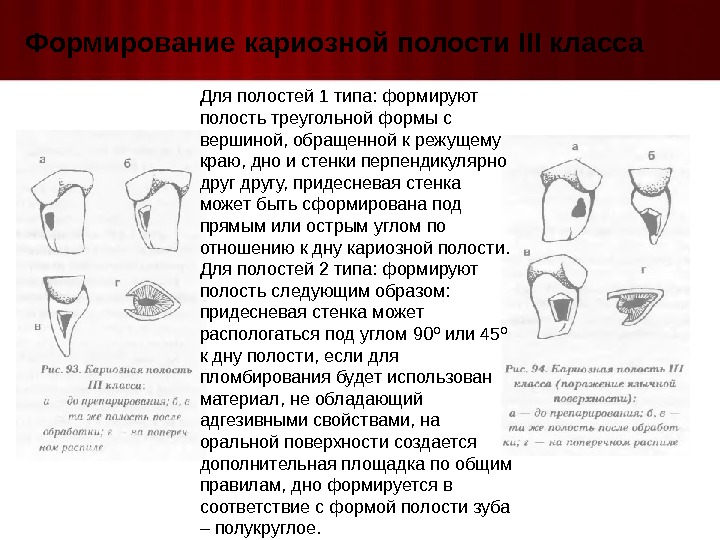

Препарирование кариозных полостей III класса: пошаговое руководство с фото